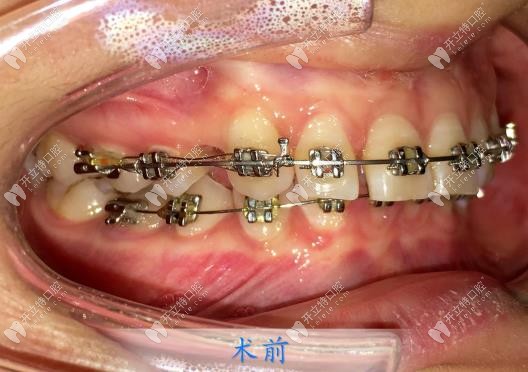

然后過了差不多半個(gè)月后,我就到院內(nèi)戴牙套了,楊醫(yī)生很細(xì)心,每一個(gè)托槽粘的都很認(rèn)真,他說這樣也是能防止后期托槽脫落帶來不必要的麻煩,我就更認(rèn)可楊醫(yī)生了!

矯正的周期是兩年,中間每個(gè)月都要復(fù)診,每次復(fù)診都是楊醫(yī)生為我加力的,直到取下牙套,結(jié)束矯正,我的牙齒都是楊永利醫(yī)生一手負(fù)責(zé)的!真的很認(rèn)真!